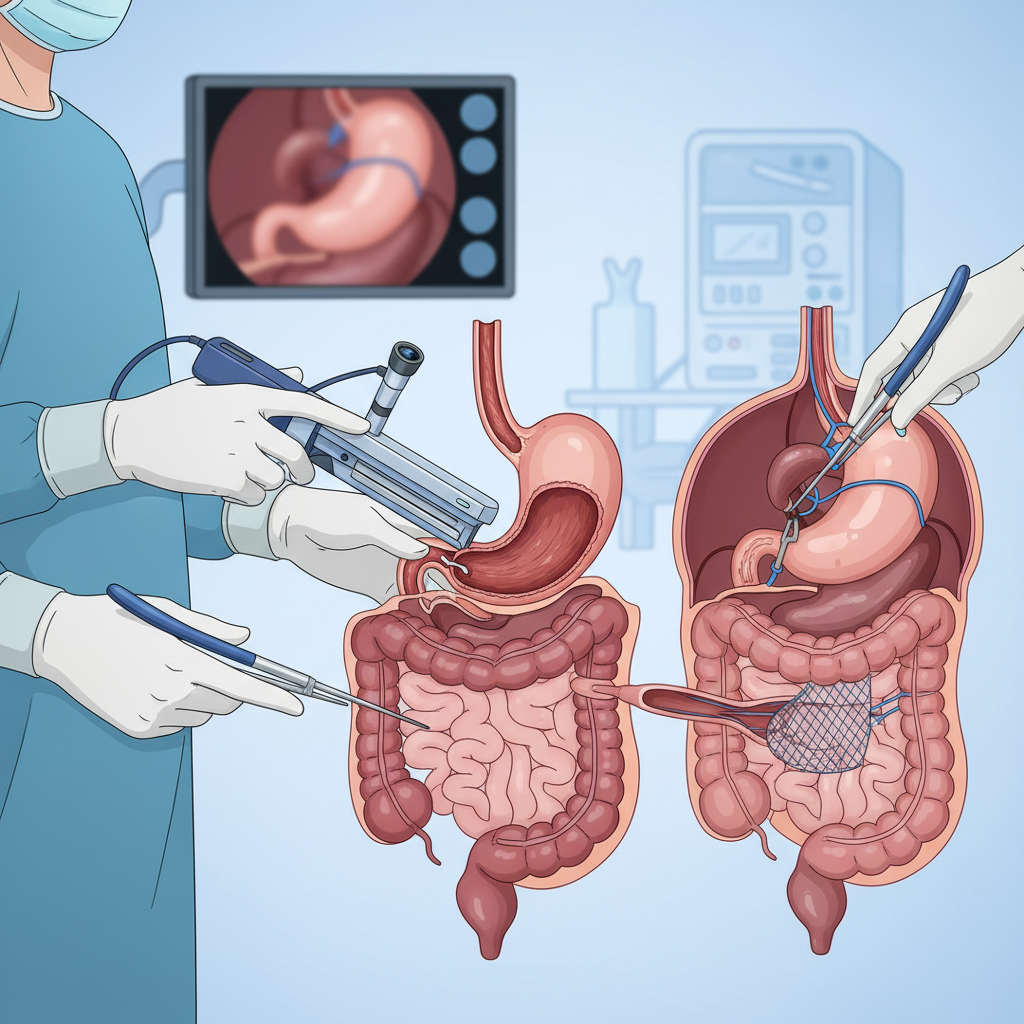

Gastroenteroloji İşlemleri: Endoskopik Tanı ve Tedavi Yöntemleri

“Hangi işlemler yapılır?” sorusunun önemli bir kısmı, ameliyathaneye girmeden yapılan endoskopik girişimleri kapsar. Bu noktada “endoskopik cerrahi” ifadesi bazen kullanılsa da, çoğu işlem teknik olarak “ameliyat” değil; endoskopla içeriden yapılan tanı/tedavi uygulamalarıdır. Yine de bazı endoskopik tedaviler ileri düzeyde olup cerrahiye alternatif olabilir ya da cerrahiyi tamamlayıcı rol üstlenebilir.

Tanısal endoskopik işlemler

- Gastroskopi: Yemek borusu, mide ve onikiparmak bağırsağı incelenir. Reflü, gastrit, ülser, kanama odağı, çölyak şüphesi gibi durumlarda kullanılır.

- Kolonoskopi: Kalın bağırsağın incelenmesidir. Kansızlık, dışkıda kan, kronik ishal/kabızlık, tarama amaçlı kolon kanseri değerlendirmesi gibi durumlarda yapılır.

- Endoskopik ultrason (EUS): Bazı merkezlerde pankreas, safra yolları ve sindirim kanal duvarı lezyonlarının değerlendirilmesinde kullanılır.

Terapötik (tedavi edici) endoskopik işlemler

- Biyopsi alma: Şüpheli alanlardan örnek alınır; tanının netleşmesinde kritik rol oynar.

- Polipektomi (polip çıkarılması): Kolonoskopi sırasında poliplerin alınması, kolon kanseri riskini azaltabilir. Hastalar bunu sıkça “ameliyat oldum mu?” diye sorar; çoğu zaman bu işlem endoskopik tedavidir.

- Kanama durdurma: Endoskopi ile klips, enjeksiyon veya yakma yöntemleri uygulanabilir.

- Darlık genişletme ve stent: Özofagus/kolon gibi bölgelerde darlık varsa balonla genişletme veya stent uygulanabilir.

- ERCP: Safra ve pankreas kanallarındaki taş, darlık veya tıkanıklıkların tedavisinde kullanılan ileri bir işlemdir (taş çıkarma, sfinkterotomi, stent gibi uygulamalar).

Bu işlemler çoğu zaman sedasyon (uyku hâli) ile yapılır ve hastanın durumuna göre aynı gün taburculuk mümkün olabilir. Yine de her girişimin riskleri ve hazırlık gereklilikleri olduğundan, hekim önerileri birebir takip edilmelidir. Daha fazla bilgi için: Endoskopi nedir? ve Gastroskopi nedir? yazılarımıza göz atabilirsiniz.

“Endoskopik cerrahi” ile laparoskopik cerrahi aynı mı?

Hayır. Karışıklığın en sık yaşandığı yer burasıdır:

- Endoskopik işlemler: Ağızdan veya makattan girilerek, sindirim kanalının içinden yapılan girişimlerdir.

- Laparoskopik cerrahi: Karın duvarından küçük kesilerle girilerek, karın içindeki organlara yönelik yapılan “kapalı ameliyat”tır.

Her iki yaklaşım da minimal invaziv olabilir; ancak hedeflenen alan, kullanılan cihazlar ve tedavinin kapsamı farklıdır.